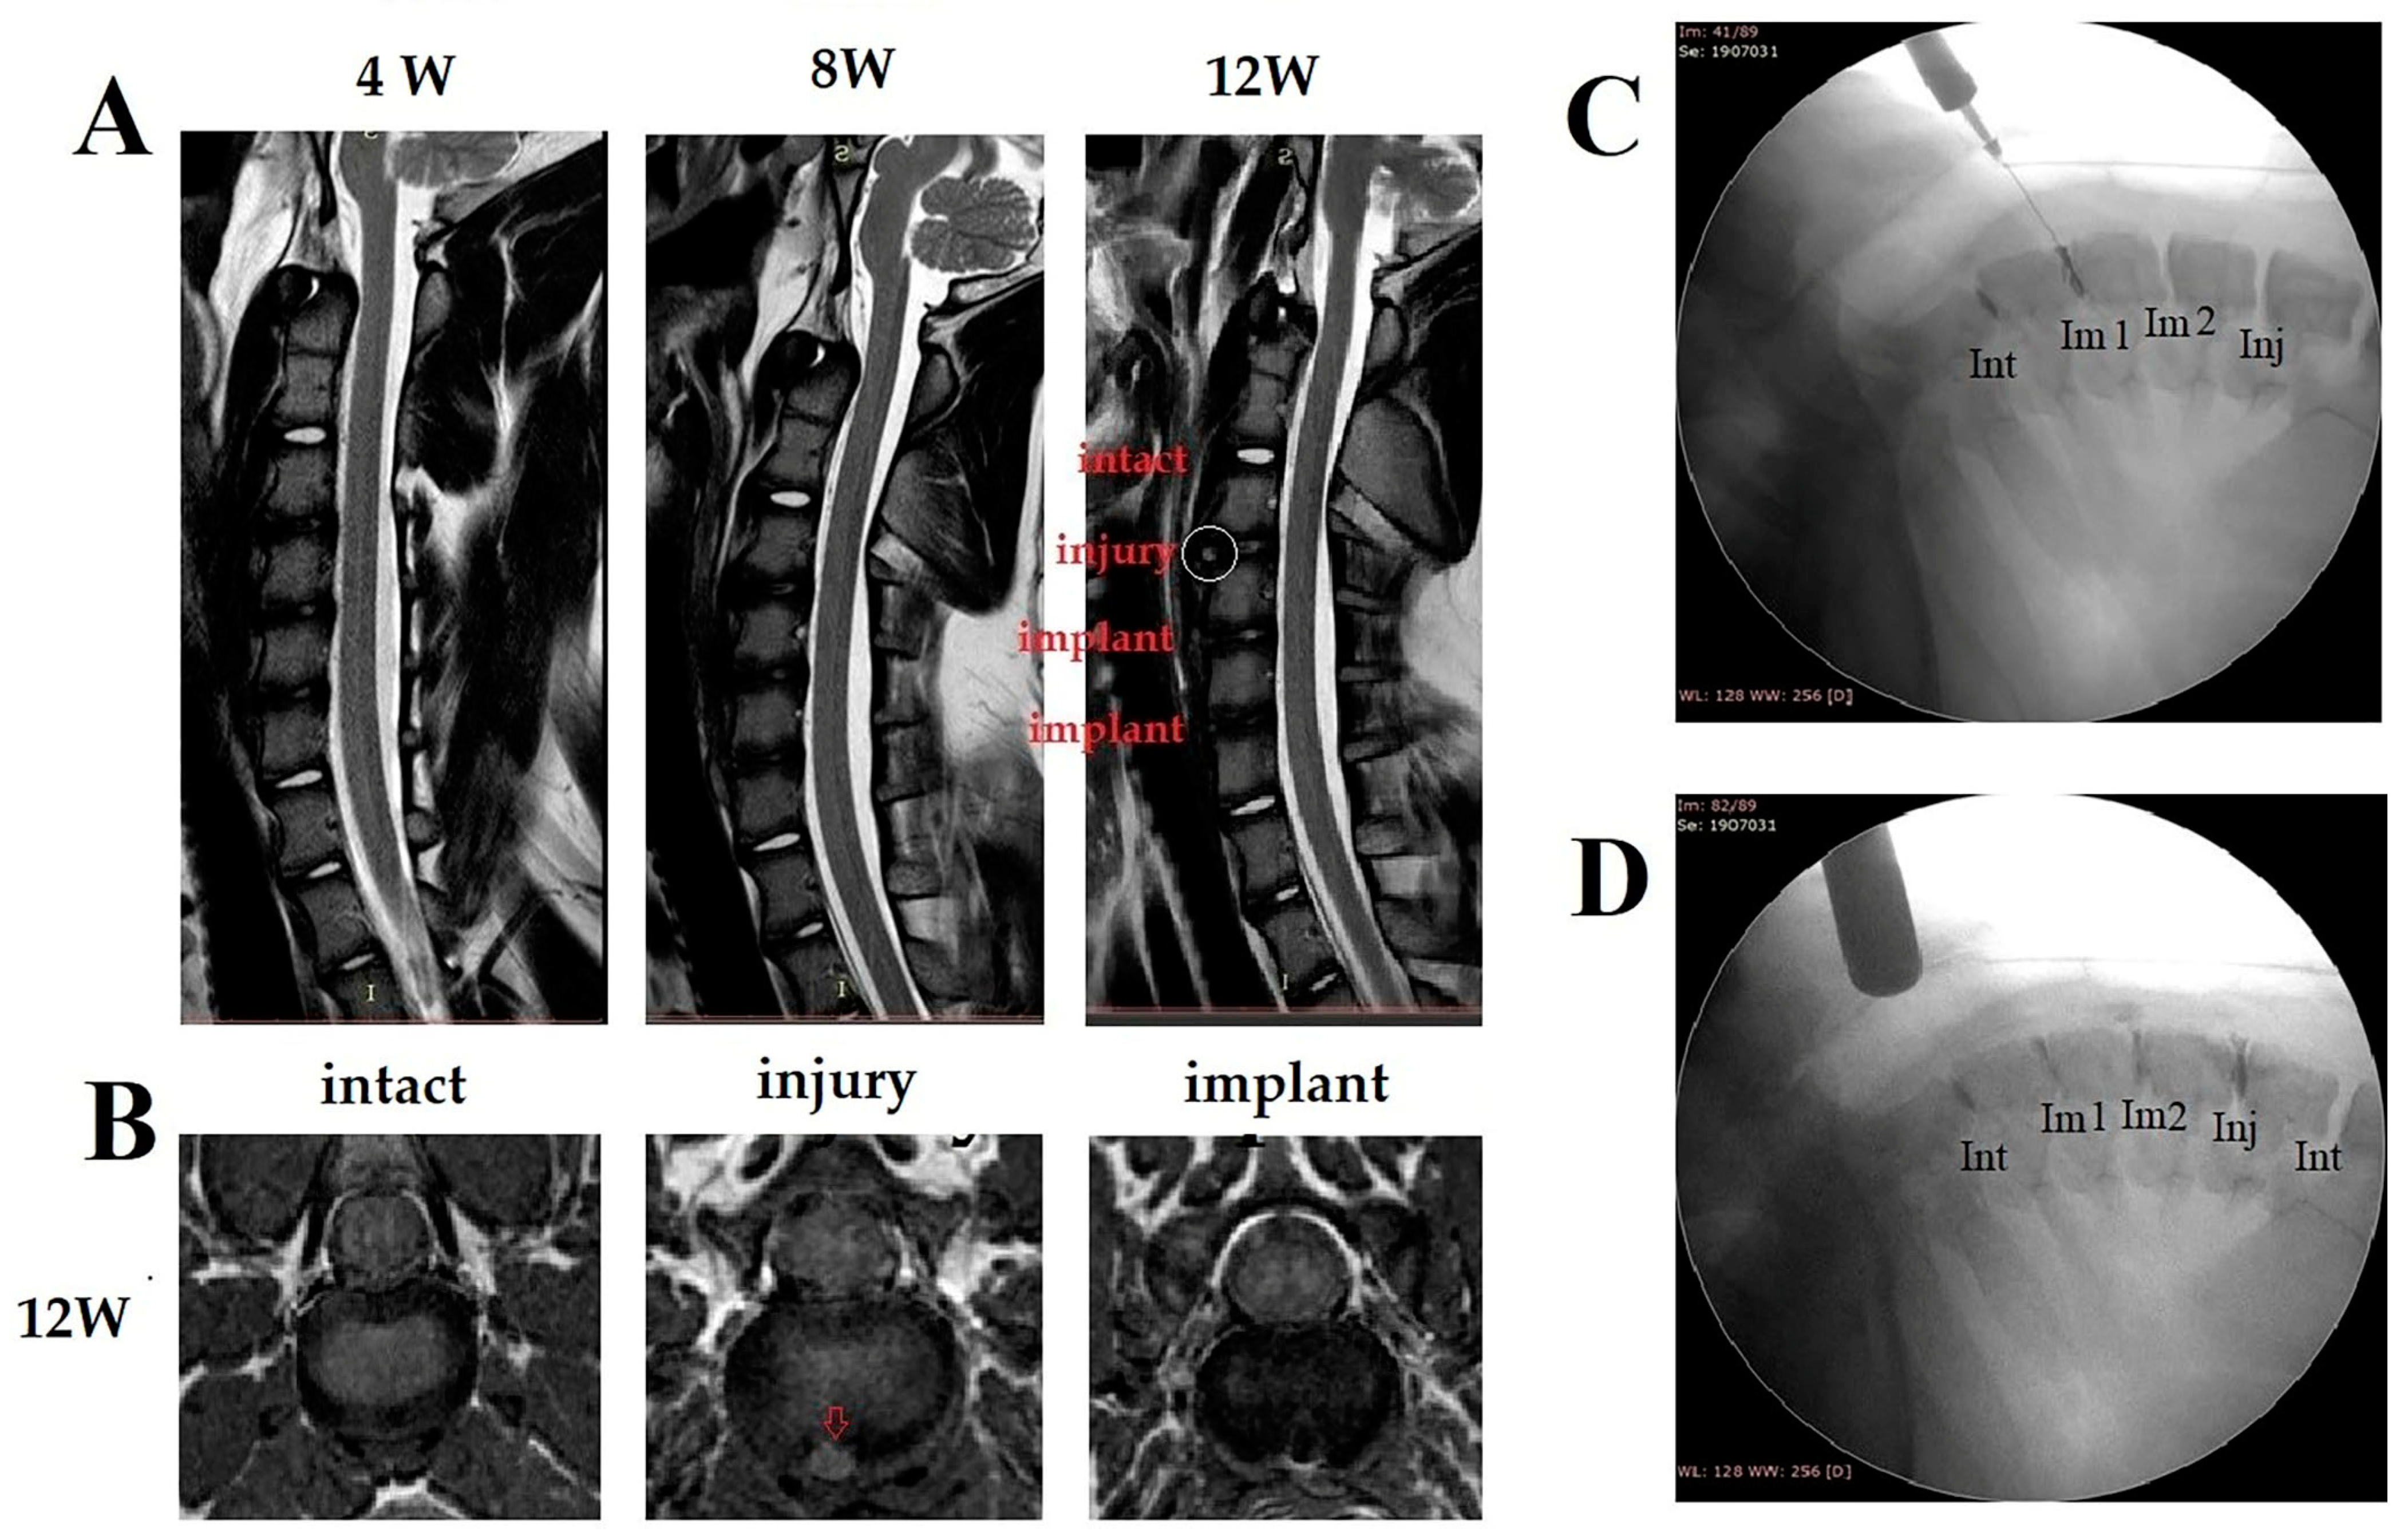

3.3.1. X-ray Imaging, MRI and Discography